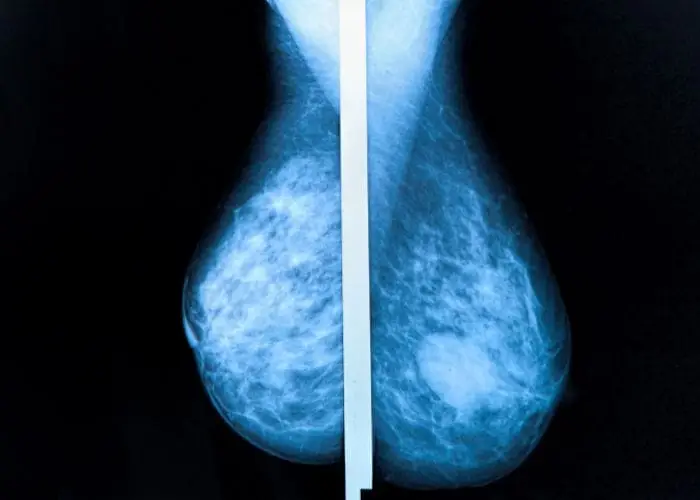

We provide online interpretation and reporting of digital and computer-aided mammogram studies. Our reporting radiologists hold certifications and high-quality, professional assessments.